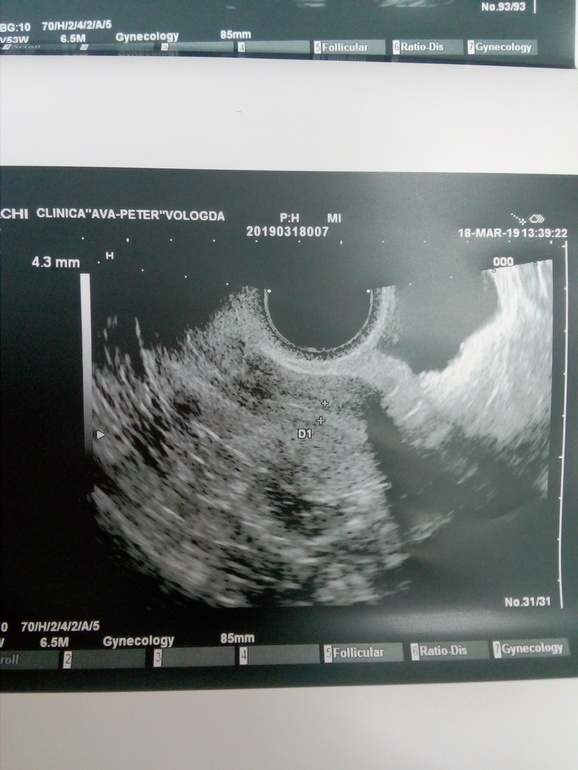

Здравствуйте девушки. Ситуация следующая. Идет первый цикл стимуляции клостилбегит по 1 таб в день со 2 по 6 дц. Врач сказала что перед приемом узи делать не надо, первое через пару дней после последней таблетки. Сегодня пошла на узи и пипец... На левом яичнике киста 29мм. Видимо с прошлого цикла. ХЗ что делать то теперь??? Можно кто сталкивался с таким.

Фото узи

Спасибо за ответ. Вот и не знаю что и думать. В принципе думаю вряд ли так фолик быстро вымахал. Я переживаю за то что не начала бы киста еще больше расти. Вот еще смущает что она почему то на узи как то не как киста выглядит, что то уж больно края не ровные

Теперь то буду знать. Я что сейчас делать не знаю. Странно что киста не ушла с М. была киста в первом цикле после лапары и ушла после М. И как то уж она выглядит странно, края не ровные какие то.